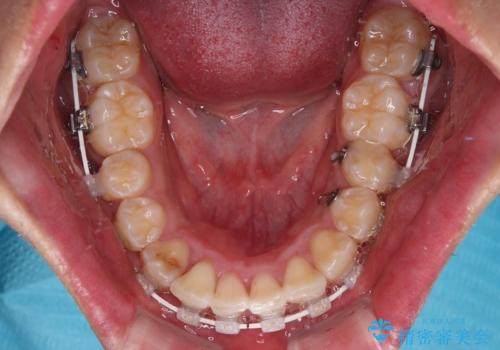

- 矯正装置

- 審美装置

- 2年5ヶ月

骨格的な左右差が大きかったため、上下の正中のズレや、左右奥歯の咬み合わせなどは妥協的な仕上がりとなりました。

骨格的なズレに対応するにはワイヤー矯正が至適であり、マウスピース矯正は選択しないようにお話をしました。